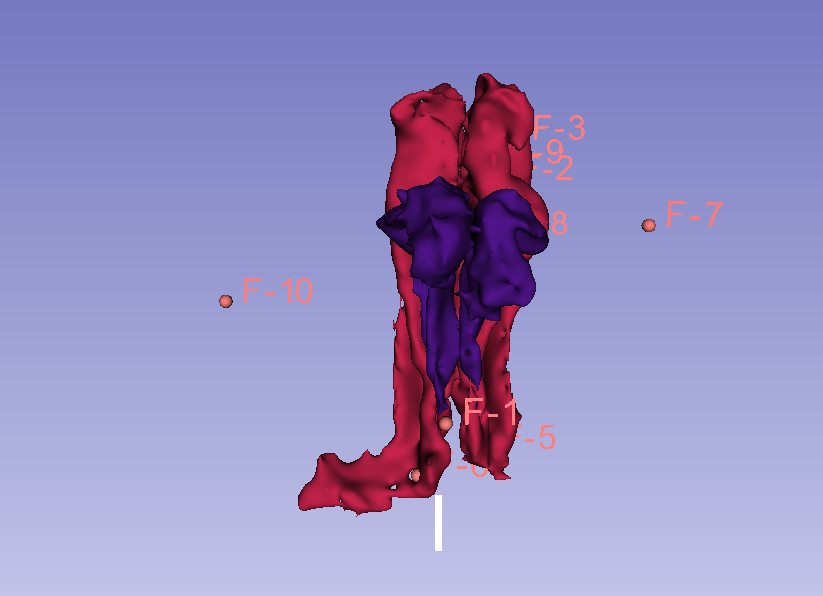

- The two structures that have been segmented are:

- Subcallosal area (SC)

- Medial border: hemispheric margin

- Lateral border: grey-white matter border

- Superior border: corpus callosum

- Inferior border: inferior hemispheric curvature (45º line)

- Anterior border: slice A 31.900mm

- Posterior border: slice A 15.116 mm

- Orbito Frontal Cortex (OFC)

- Medial border: olfatory surcus

- Lateral border: orbital surcus

- Superior border: grey-white matter border

- Inferior border: hemispheric margin

- Anterior border: right hemisphere A 55.800mm, left hemisphere A 56.500mm

- Posterior border: right hemisphere A 8.200mm, left hemisphere A 7.500mm

- In the OFC segment the medial and two lateral segments have been merged into a single segment. The segmentation has been done manually, tracing the contours of the desired segments between the defined anterior and posterior boundaries on the coronal view.

| Anterior view |

| Superior view |

| Left view |